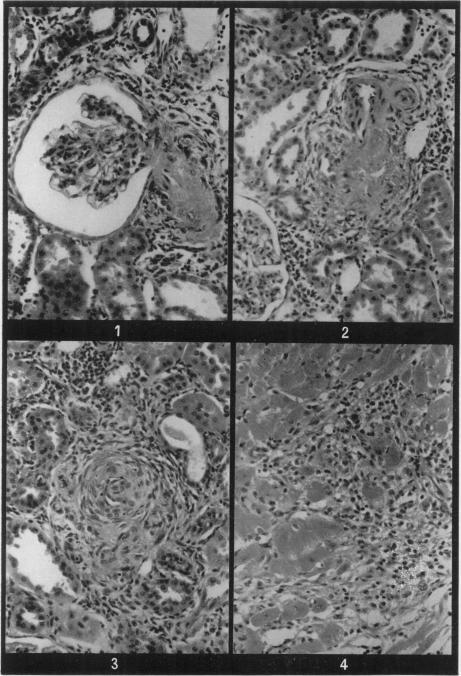

Reasons are given for suspecting that one component in the injury to small arteries and arterioles in accelerated hypertension may be an immunological mechanism. To test this hypothesis, rats were subjected to a deoxycortone/unilateral nephrectomy/salt load regime and simultaneously treated with one of three immunosuppressive procedures: cyclophosphamide, whole-body X-irradiation or rabbit anti-rat lymphocytic serum (ALS). Histological evidence of a depressive effect on the lymphoreticular tissues was obtained but interference with the normal development of arterial and arteriolar necrosis and of plasmatic vasculosis varied. ALS displayed no protective effect whatever. Cyclophosphamide interfered with the development of hypertensive vascular lesions but caused, by itself, a high mortality among non-hypertensive control animals. X-irradiation prevented hypertensive arteriolar injury but probably exerted this effect by an action distinct from blood pressure since animals so treated developed marked left ventricular hypertrophy, perhaps due to the combined hypertension-provoking insults of deoxycortone and irradiation.